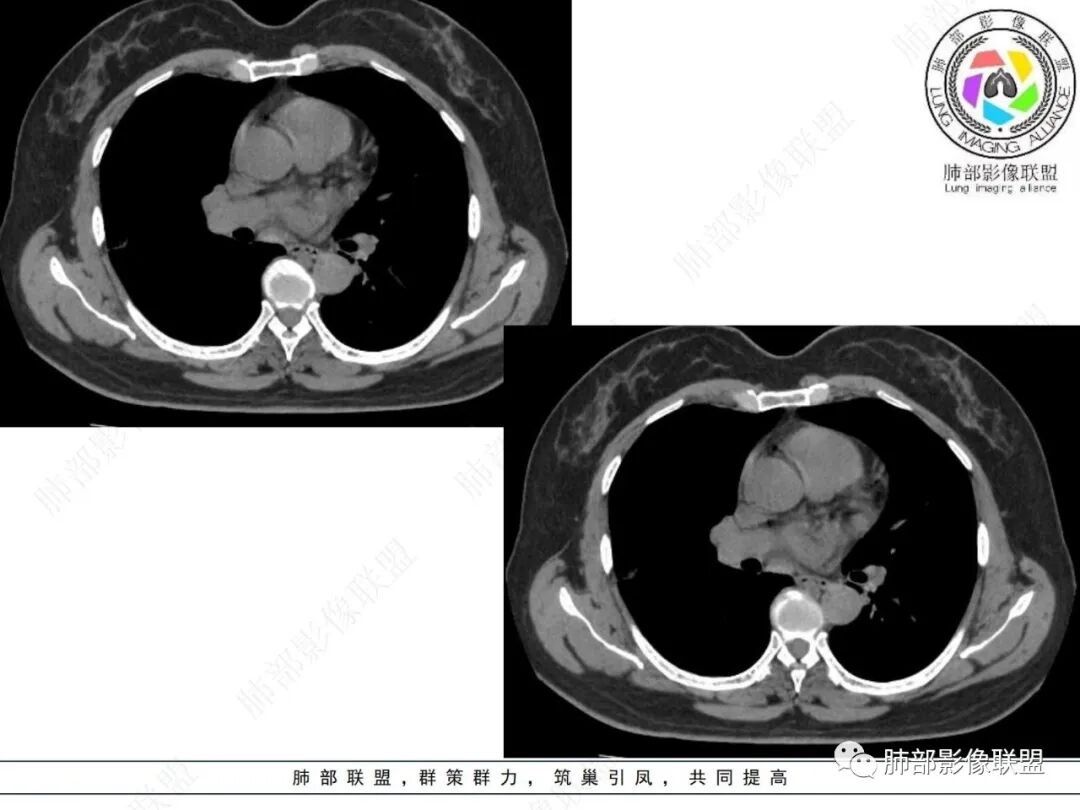

2.影像特点:

右肺上叶胸膜下混合磨玻璃团片影。

周围磨玻璃部分间杂条索状高密度区,密度欠均匀(可疑重力分布趋势),其磨玻璃影边界大多较清楚或可分辨,部分“L型”边缘,提示小叶间隔阻挡可能。血管穿行自如,可疑远端支气管进入。

实性部分较密实,不规则,隐约见棘突或刺状突起,未见钙化、空洞或液化区,实性边缘可见斑状略低密度间隙(借用王兆宇老师课件,称其呈“松软”的形态)。动脉期实性部分较明显不均匀强化,如果有完整增强图,还可以观察内部血管情况。

纵隔窗相对肺窗病灶相对小,仅部分实性影呈现。病灶张力不高,相邻胸膜增厚(糊墙),未见明显胸膜牵拉凹陷。

未见卫星病灶,远处未见磨玻璃结节影。

双肺门及纵隔未见明显增大淋巴结。心包及胸腔未见积液。